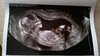

Oliwiapatrycja śliczna dzidzia [emoji5]️ ładnie już urosła [emoji4]

Dzięki :-) i teraz tak się przyglądam na zdjęcie z otwartą buzia że pod nogami coś zwisa chyba :-/ chyba kolejny mój chłop@oliwiapatrycja śliczna dzidzia![]()